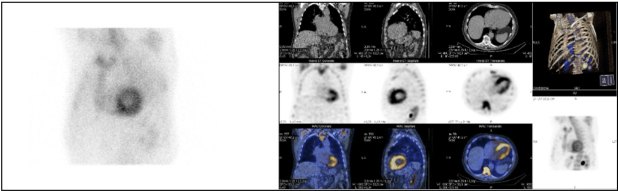

Se realizó una cardio-resonancia magnética (CRM), la cual informó de hallazgos compatibles con miocardiopatía infiltrativa, planteando como primera posibilidad amiloidosis cardíaca (Fig. 1). Finalmente, la gammagrafía con 99mTc-HDP y SPECT/TC torácico reveló captación del radiotrazador por parte de ambos ventrículos, de carácter difuso y grado 3 en la escala de Perugini, siendo estos hallazgos altamente sugestivos de afectación por amiloidosis cardíaca por acúmulo de transtirretina (TTR)(1,2,3) (Fig. 2).